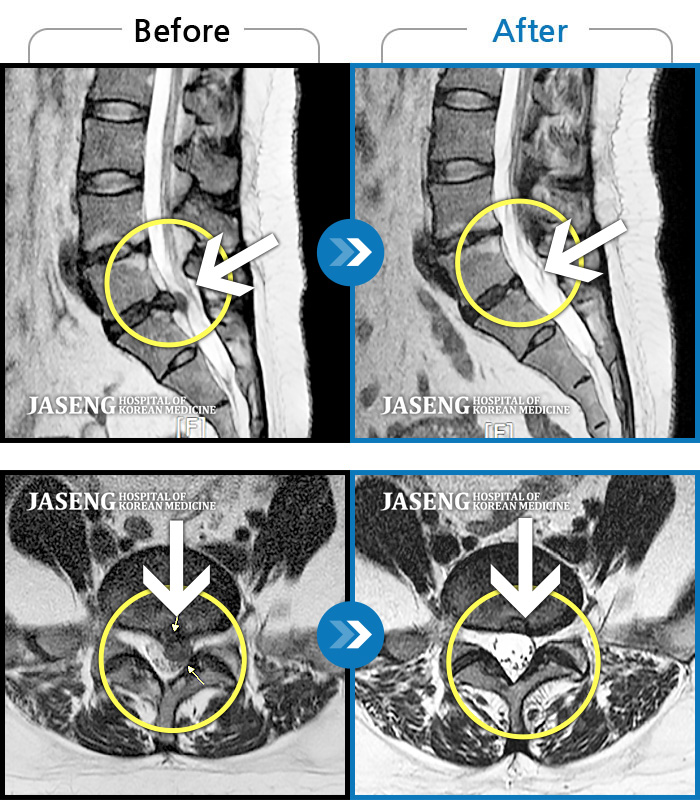

허리디스크

도움받은 사례

인천 · 조남훈 원장

재채기 하고 나서 다리에 힘이 안들어가요.

촬영시기

2021.11.10 ~ 2024.11.26

2024.12.04

조회수 442